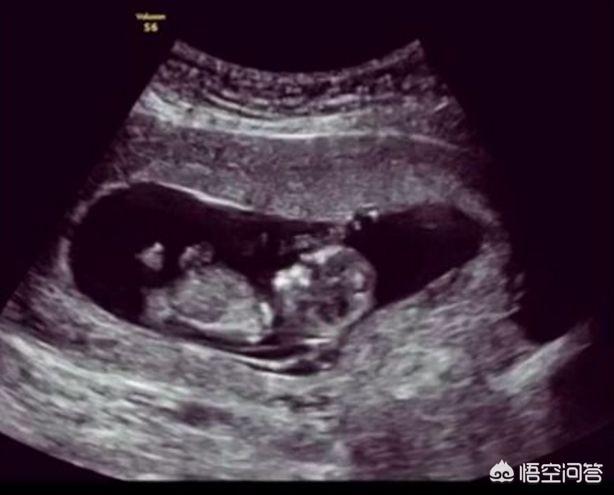

- Frühschwangerschaft: Der Ultraschall kann eine Eileiterschwangerschaft ausschließen, das fötale Herz und die Knospen überprüfen, Anomalien des Babys rechtzeitig erkennen und eine Fehlgeburt verhindern.

- In der Mitte der Schwangerschaft: Mit Hilfe der Ultraschalluntersuchung kann festgestellt werden, wie sich die meisten Organe im Körper des Fötus entwickeln, und die Geburt eines Fötus mit schwerwiegenden Fehlbildungen kann vermieden werden.

- Spätschwangerschaft: Eine Ultraschalluntersuchung kann die Größe des Fötus beurteilen und eine Grundlage für die Wahl des Entbindungsmodus liefern, wodurch das Risiko von Wehen erheblich verringert wird.

Darüber hinaus sind während der Schwangerschaft neben den Routine-Ultraschalluntersuchungen folgende spezielle Ultraschalluntersuchungen erforderlich.

I. Obligatorische Ultraschalluntersuchung während der Schwangerschaft:

1. NT-Ultraschall

Die Untersuchung muss unbedingt zwischen 11 Wochen und 13 Wochen + 6 Tagen der Schwangerschaft durchgeführt werden.

2. das Screening auf fötale systemische Fehlbildungen

Ultraschall des fetalen Herzens, eine detaillierte Untersuchung des fetalen Herzens, wenn die Möglichkeit einer angeborenen Herzerkrankung in Betracht gezogen wird.